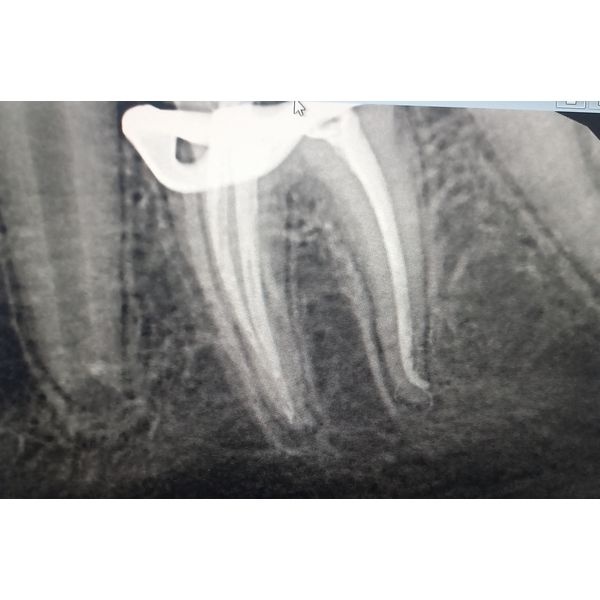

Определили рабочую длину корневых каналов и сделали рентгенографию, чтобы её подтвердить. Затем каналы обработали, высушили и запломбировали. С помощью рентгенографии проверили, что корневые каналы запломбированы полностью до физиологической верхушки.

Затем обработали оставшуюся полость зуба, изолировали устья корневых каналов, обработали зуб под стандартную стальную коронку, сняли коффердам и примерили коронку. На рентгенограмме было видно, что коронка прилегает герметично до анатомической шейки зуба. Поэтому коронку сняли, обработали и затем зафиксировали.